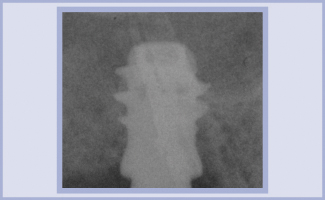

Paziente di sesso maschile di anni 36, nessuna notizia anamnestica particolarmente rilevante. La radiografia pre-operatoria dell’area edentula da riabilitare, zona 16, mostra una scarsa disponibilità ossea verticale. Si esclude un intervento di mini rialzo di seno optando per l’impiego di un impianto corto 6.5 Exacone® (fig. 1) in tecnica monofasica poiché, al momento dell’inserimento, la stabilità primaria è eccellente. Dopo cinque mesi si procede alla rimozione del tappo di guarigione, alla verifica della guarigione dei tessuti ed alla presa dell’impronta in polietere (Impregum™ 3M ESPE). Sopra il transfer si posiziona l’analogo con il suo pin. Le componenti (transfer, analogo, ecc.) che si utilizzano sopra l’impianto corto sono le stesse dell’impianto 4,1, come si evince dalle foto (figg. 3-6). Dopo aver sviluppato il modello, condizioniamo il gesso per migliorare i volumi del dente che andiamo a progettare, non solo per una questione estetica ma anche per un maggior comfort per il paziente (figg. 7, 8). Si procede alla digitalizzazione del modello master tramite scansione con dispositivo Inlab Sirona (fig. 9).

- Fig. 1 – Rx post-operatoria